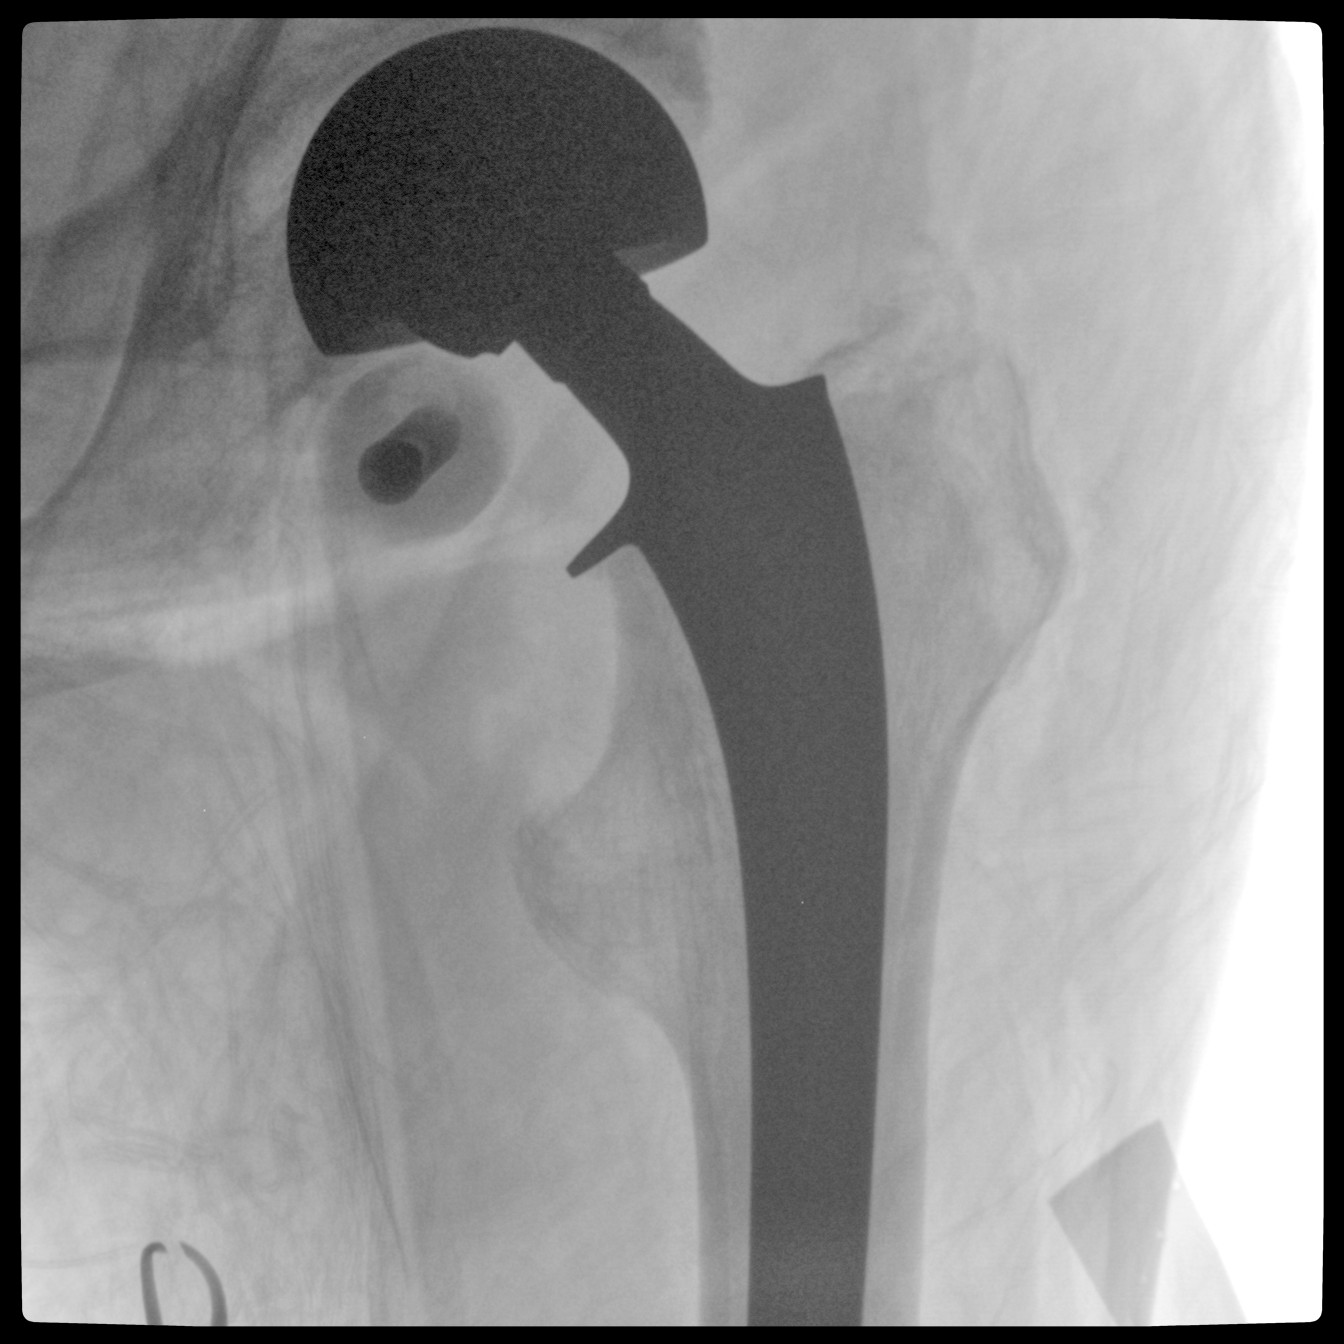

Clinical picture

臨床圖片

配備了兩種平板尺寸,大尺寸動態(tài)平板探測器成像面積較傳統(tǒng)平板探測器提升了25%以上,在視野需求大的手術(shù)中,便于醫(yī)生更好定位病灶點(diǎn),規(guī)劃手術(shù)方案,減少因視野范圍不足而多次透視、點(diǎn)片造成的不便。